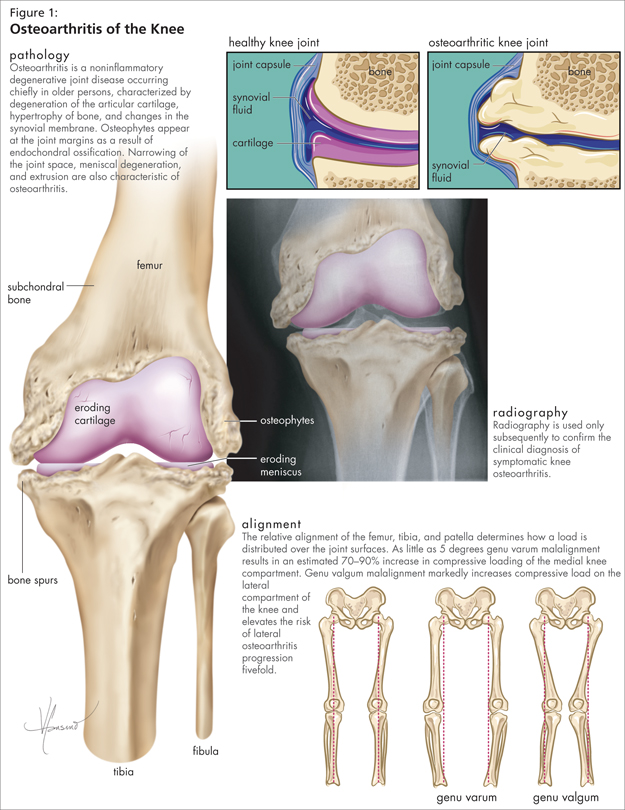

0908cmefig1